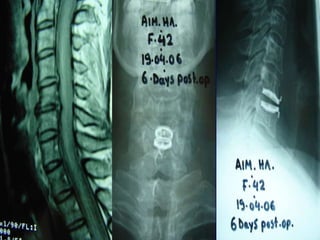

Chord compression at C4-C5 left side

Lateral view after

Prodisc-C implantation

ΑΡ view after

Prodisc-C implantatio

MRI pre-surgery.

DDD multilevels -

Chord

compression at C4-

C5

Chord compression

at C5-C6 pre-surgery

Flexion and Extension

after Prodisc-C

implantation at level C5-

C6

Prodisc – C in neutral

position and in lateral

bending